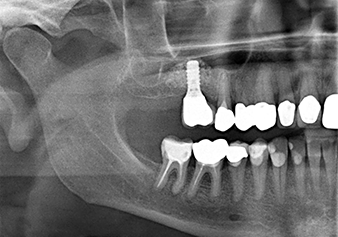

Pour mettre en place le matériau d’augmentation en douceur en direction du sinus maxillaire, l’implant est inséré manuellement très lentement (Fig. 9). Pendant l’opération, la membrane est poussée de nouveau dans la direction crânienne. Au bout de deux mois, le site chirurgical cicatrise sans signes d’irritation. Six mois plus tard, la radio de contrôle révèle une augmentation significative de l'opacité indicative de l’ossification (Fig. 10). La restauration prothétique est réalisée avec une couronne métallo-céramique.